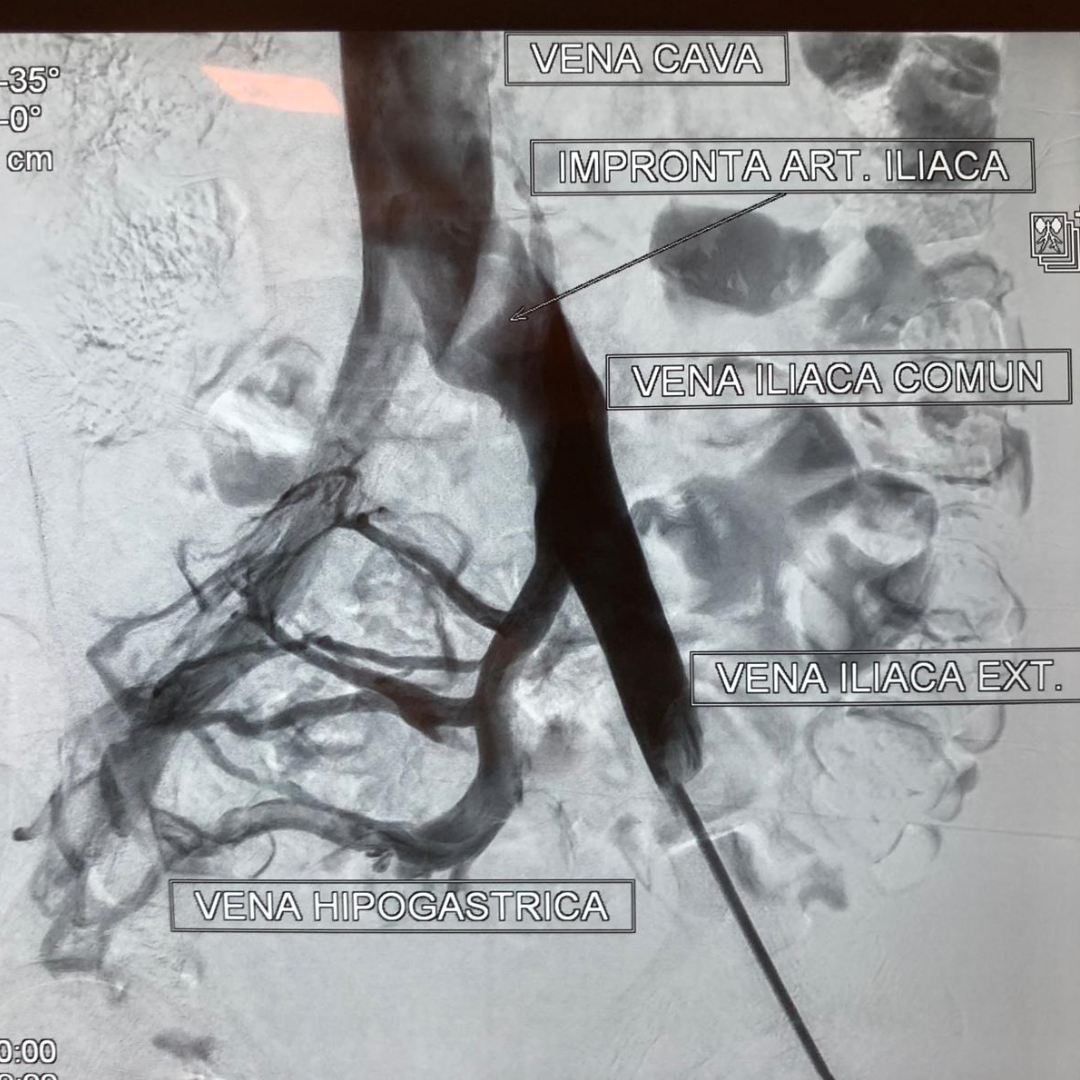

Antes: Oclusión bilateral ilíaca

Oclusión de ambas venas ilíacas/Sindrome de congestión pélvica

• Reconstrucción venosa profunda Tratamiento especializado de obstrucciones iliofemorales, secuelas postrombóticas y enfermedad venosa compleja, orientado a restaurar función y mejorar calidad de vida.